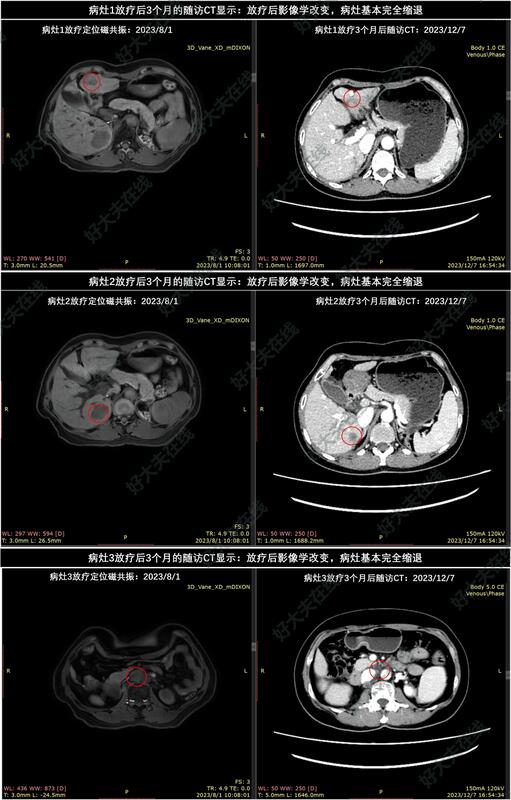

患者于2023年8月完成SBRT放疗:50Gy/8Fx(处方BED=81.3Gy,3个PTV内平均BED依次为112.6Gy,107.5Gy,96.4Gy)。

放疗后18个月的随访CT显示:放疗后影像学改变,3个病灶都持续受控。患者肝功能正常,目前生活质量良好。